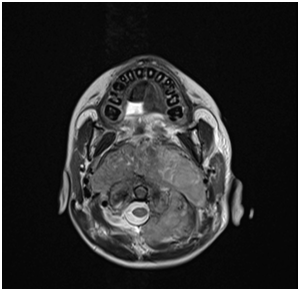

7 years old boy presented with history of left neck mass, headache and weight loss for 1-month duration, with limited range of motion of the neck and increasing pain in that region for 5 days before he was referred to our hospital. Physical examination revealed left upper cervical swelling measuring 5x6 cm in diameter, firm in consistency and attached to the underlying structures, no neurological deficit of signs of respiratory compromise was observed. His initial laboratory results are shown in Table 1. Cervical lymph node biopsy revealed reactive lymph nodes, negative for granulomata and negative for malignancy. Magnetic resonance imaging (MRI) of the neck (Figure 1) showed evidence of perivertebral/retropharynegal large multilobulated soft tissue mass measuring about 7.9x8.7x6.9 cm in transverse, craniocaudal and at the posterior dimensions respectively, extending in the nasopharyngeal region, and extending opposite to the skull base, clivus and upper cervical vertebra body posteriorly with the extension through the neural foramina of C1 and C2 vertebrae and causing bony erosions, extending into the spinal canal, however the signal intensity of the spinal cord was preserved, with narrowing of the right vertebral artery and questionable tumour involvement at the level of C1. Superior extension of the mass is seen obstructing the nasopharynx, anteriorly the mass is seen compressing the nasopharynx and exerting mass effect on the oropharynx with no patent airway seen around endotracheal tube. Infiltration of the hard palate and palatine tonsils were seen, laterally the mass seen compressing the carotid vessels bilaterally with suspicion of marked compression and occlusion of the left jugular vein, however the carotid arteries were patent. The patient underwent incisional biopsy of the retropharyngeal mass and bilateral bone marrow aspiration & biopsy. During surgery patient was electively intubated and due to difficulty in extubating and critical obstructed airway a tracheostomy tube was inserted to ensure patent airway. Histopathological examination of the retropharyngeal mass showed small blue cells with scant cytoplasm (Figure 2). Immunohistochemical studies showed that tumor is positive for CD99 and Vimentin, negative for Myogenin, TTF-1, Pankeratin, Desmin, Chromogranin,CD45, Synaptophysin, SMA, MSA ,CK7,EMA,CD56, CD34, and PAX5. Fluorescence in situ hybridization (FISH) study showed fusion of the ESWR1/FLI1 genes associated with the translocation t(11;22)(q24.3;q12.2) Thus radiological, histological and immunohistochemical finding were confirmatory of Ewing sarcoma of the retropharyngeal space. Bone scintigraphy showed no evidence of bone metastasis. As incidental finding on CT abdomen revealed a single hypertrophied right kidney with mild hydronephrosis. Renogram was done and showed partial obstruction, Later patient developed acute renal injury and anuria, ultrasound kidney showed severe hydronephrosis with obstruction. His case was discussed with the infectious disease and nephrology physicians and the decision was made to insert double J stent under interventional radiology, signs of renal function recovery were seen in the next 2 days. Patient started on European Ewing tumour Working Initiative of National Group 99 (EURO-E.W.I.N.G99) protocol, ended first cycle of chemotherapy that contained vincristine, ifosfamide, doxorubicin and etoposide and supported with G.C.S.F (VIDE), with acceptable tolerability. Planned for evaluation after 2 cycles for the local control option.

Figure 2 MRI of the soft tissue of the neck showing a large destructive soft tissue mass measuring about 7.9x8.7x6.9cm in diameter (coronal and axial view).